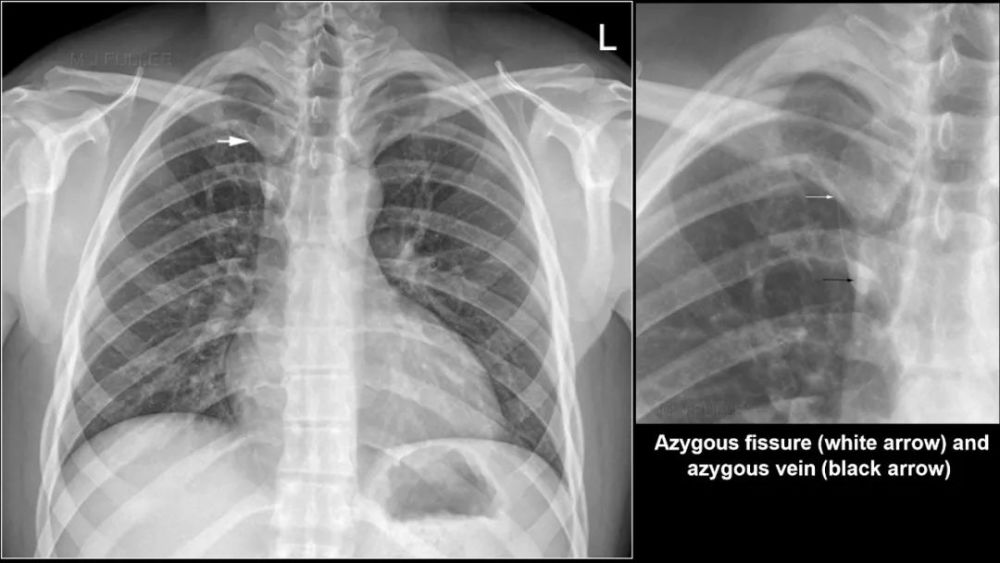

左侧水平裂

Left minor fissure

CT上的检出率为:8% , AP胸片为1.6%

左侧水平裂将舌叶从下叶其它部分分隔出来 舌叶仍然保留其上段和下段 , 不同于右肺中叶 内侧段和外侧段 , 因此左肺的段解剖保持完整